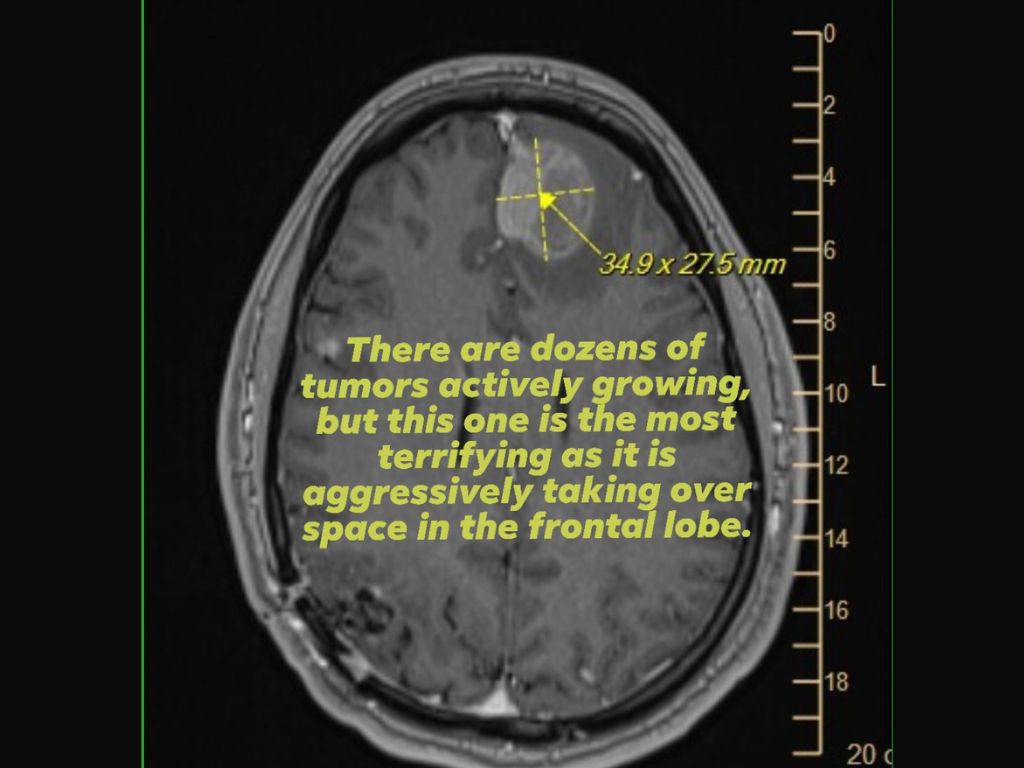

Come prova, ha anche allegato un'immagine di una scansione cerebrale (risonanza magnetica) che mostrava un tumore aggressivo del lobo frontale, mentre implorava il sostegno o l'aiuto dei dirigenti di Epic Games, che hanno preso le decisioni chiave riguardo ai licenziamenti.